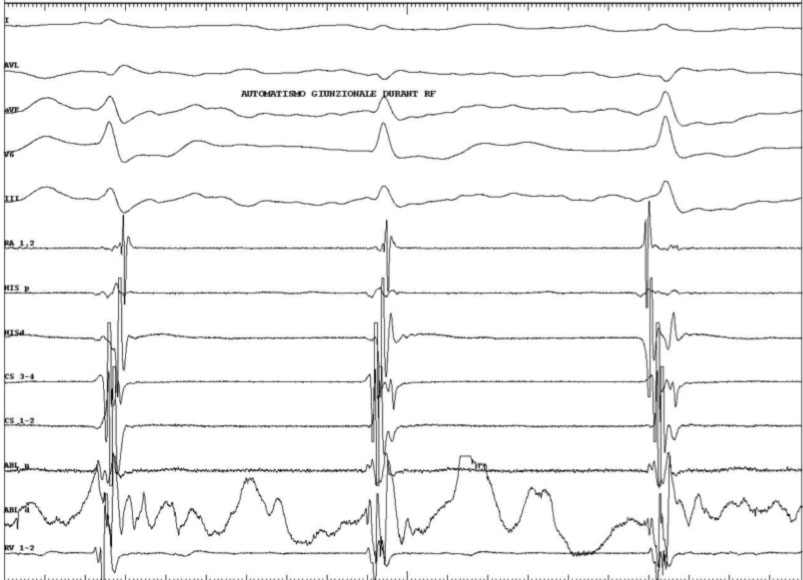

Generalmente la porzione di annulus tricuspidalico compresa tra l’ostio del seno coronarico ed il fascio di His viene suddivisa in tre segmenti: posteriore (vicino all’ostio del seno coronarico), medio, e anteriore (vicino al fascio di His). Il catetere viene posizionato lungo la valvola tricuspide e fatto scorrere finché non vengono registrati il potenziale atriale e quello ventricolare con la deflessione atriale più grande della deflessione ventricolare. A questo punto vengono erogate RF, e generalmente se la posizione del catetere è corretta è possibile osservare dei battiti giunzionali o una tachicardia giunzionale. Se dopo 10-15 secondi di RF non compaiono battiti giunzionali è bene interrompere l’erogazione e cambiare la posizione del catetere ablatore. Se al contrario compaiono i battiti giunzionali è bene erogare RF per altri 30-60 sec.